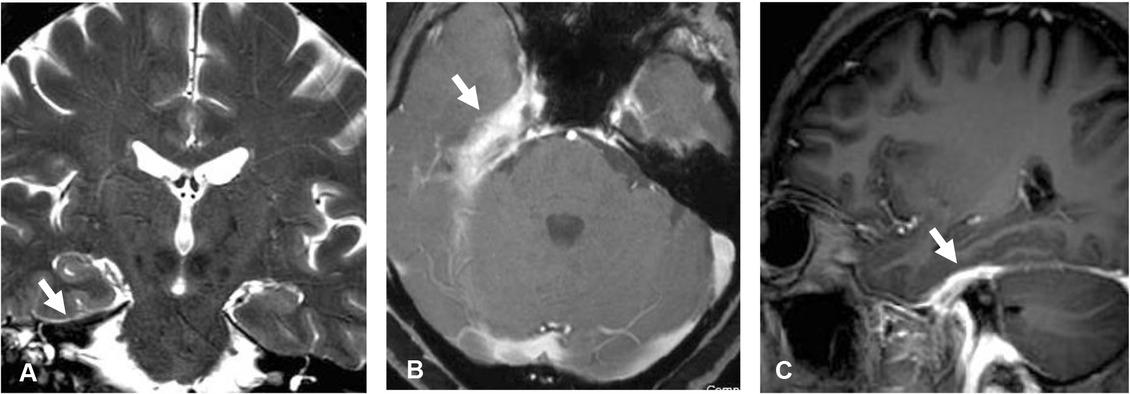

Figure 3

IgG4-related pachymeningitis. Coronal T2-weighted image (A) shows dark intensity dural thickening involving right tentorium cerebelli (arrow). Axial (B) and sagittal (C) gadolinium-enhanced T1-weighted images demonstrate mildly heterogeneous enhancement of the thickened dura involving right medial temporal region, right Meckel’s cave, and along anterior part of right tentorium cerebelli (arrow).